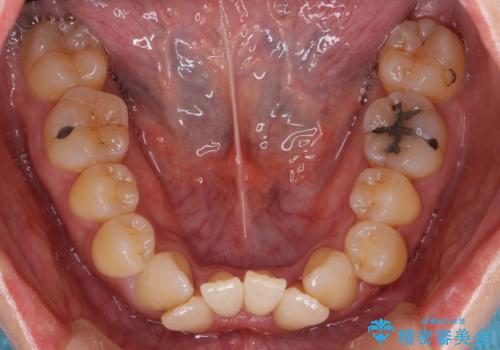

成人の矯正でしたので、矯正治療前にしっかり必要な歯周病治療を行い、状態が改善してから開始しました。

- 治療中は歯磨きがしにくくなるため、虫歯や歯周病になりやすくなります